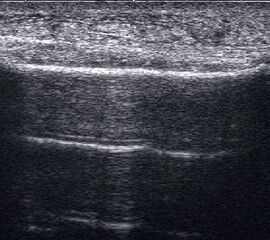

Achillessehne

Achillessehnenrupturen

Lagerung: Bauchlage, ggf. Sprunggelenk mittels Rolle unterlagert.

Schnittführung: LS über der Achillessehne, ggf. in leichter manueller Vorspannung der Achillessehne, damit diese parallel zum Schallkopf optimal eingestelt werden kann (Abb. 52).

Referenzstruktur: Direkt unter der Haut und der dünnen Subkutis liegt echogen und straff parallel die Achillessehne mit ihrem echogenen Peritendineum (Abb. 53), Tuber calcanei.